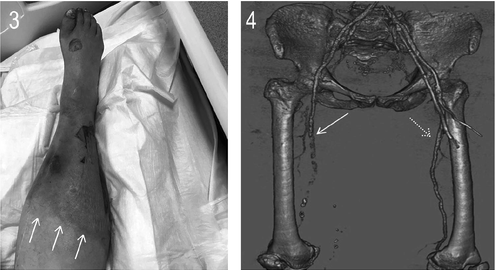

Images in Vascular Medicine: Peripheral artery thrombosis in critically ill patients with #COVID19 ow.ly/BwbE50AOMDA

VMJ_SVM's tweet image. Images in Vascular Medicine: Peripheral artery thrombosis in critically ill patients with #COVID19

ow.ly/BwbE50AOMDA